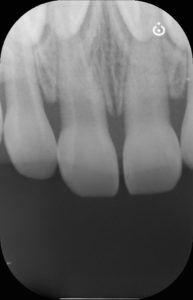

受傷から8ヶ月後

脱臼した歯の色は周囲と殆ど同じくらいに戻りました。

レントゲン所見も異常はないため、追加の処置等は行わず治療終了としました。